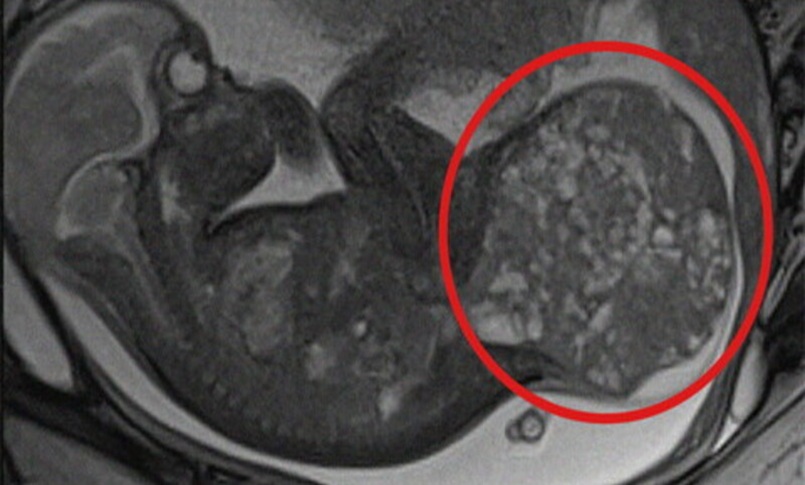

Alla nascita pesava quasi due chili, ma portava con sé un tumore di ben 800 grammi, pari a oltre la metà del suo peso corporeo effettivo (1,1 kg). Grazie a un intervento intrauterino salvavita, effettuato mentre era ancora nella pancia della mamma e, subito dopo il parto, a un’operazione chirurgica di rimozione della massa, oggi la piccola – nata prematura alla 30esima settimana di gestazione – è in buone condizioni di salute e sta per tornare a casa con la famiglia.

La grande massa rimossa, un teratoma sacro-coccigeo, è una rara neoplasia che si sviluppa nella parte terminale della colonna vertebrale e colpisce circa un neonato ogni 35-40mila nati vivi. Pur essendo solitamente benigna, può comportare gravi complicanze per il feto. Tra queste il rischio di scompenso cardiaco, idrope fetale e morte intrauterina.

Nel caso specifico, alla 28esima settimana di gestazione, a seguito di una rapida e improvvisa crescita della massa tumorale, gli specialisti dei due ospedali hanno deciso di intervenire in epoca fetale con una procedura mininvasiva di lasercoagulazione ecoguidata dei vasi sanguigni della massa stessa, eseguita presso il comparto operatorio del San Pietro Fatebenefratelli. Utilizzando un laser a diodi, è stato possibile ridurre l’afflusso sanguigno al tumore, rallentandone la crescita e permettendo di prolungare la gravidanza fino alla 30esima settimana.

La gestione multidisciplinare è proseguita all’ospedale pediatrico Bambino Gesù, dove la mamma ha poi partorito con parto cesareo programmato nell’ambito del Progetto Nascita, dedicato ai nascituri affetti da gravi patologie congenite. Dopo essere venuta alla luce, la neonata – che prima dell’intervento pesava 1,9 chili – è stata immediatamente operata per rimuovere completamente il teratoma di circa 800 grammi, pari ad oltre la metà del suo peso corporeo effettivo (1,1 kg). L’operazione, della durata di circa tre ore, ha incluso anche la ricostruzione della regione sacrale.